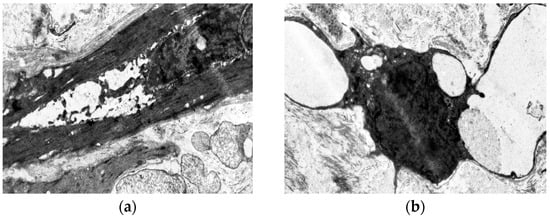

Elderly patients with VD exhibit disrupted myocyte orientation in the subintimal longitudinal layer. Connective tissue proliferation fragments muscle bundles, while the circular layer shows advanced diffuse sclerosis with scar formation (Figure 5). Ultrastructurally, degenerated “dark” myocytes dominate, surrounded by connective tissue infiltration (Figure 6).

Figure 5. Fragment of the great saphenous vein in a patient from the third age group. Hematoxylin and eosin staining. Magnification × 400. Segment of the middle layer, notable disruption of structure and orientation of smooth muscle cell bundles. Fragmentation of smooth muscle cell fibers due to the growth of connective tissue between them in the form of coarse fibrous structures.

Figure 6. Fragment of the great saphenous vein in a patient from the third age group with a disease duration of more than 10 years. Transmission electron microscopy. (a)—“dark” smooth muscle cell surrounded by collagen fibers. Magnification × 9000; (b)—vacuolization of the cytoplasm of the “dark” smooth muscle cell. Magnification × 9000.